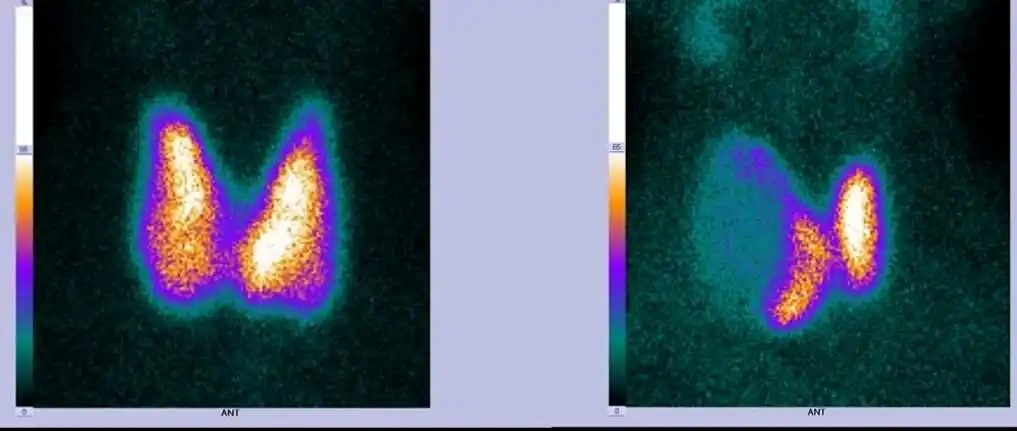

在核醫(yī)學(xué)診療中,常用的同位素藥物有Tc-99m(140keV)、I-131(364keV)、F-18(511keV)等,基于CdZnTe探測器的伽馬相機(jī),對(duì)射線能量探測范圍廣,幾乎可滿足所有藥物的檢測需求。

CdZnTe探測器能量分辨率、空間分辨率高,單位體積探測效率是NaI的2倍以上,檢測準(zhǔn)確性更高,可有效降低病人攝入的放射性藥物劑量。